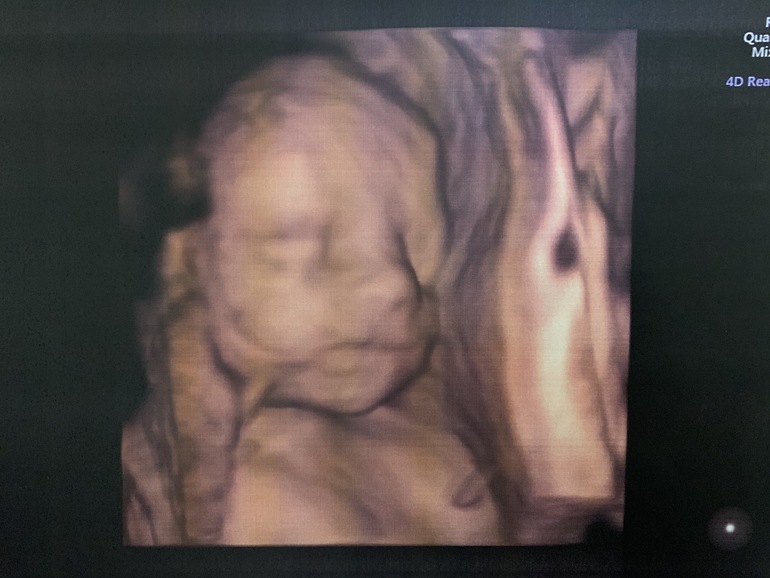

И немножко фото нашего малыша